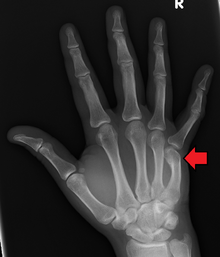

DP (PA) right hand x-ray showing fracture at the neck of fourth metacarpal bone | |

Boxer's Fracture is a colloquial term for a fracture of one of the metacarpal bones of the hand. Classically, the fracture occurs transversely across the neck of the bone, after the patient strikes an object with a closed fist. Alternate terms include scrapper's fracture or bar room fracture.

Diagnosis by a doctor’s examination is the most common, often confirmed by x-rays. X-ray is used to display the fracture and the angulations of the fracture. A CT scan may be done in very rare cases to provide a more detailed picture.